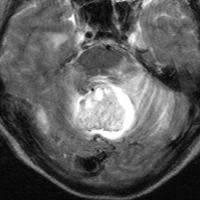

- MRIでは,のう胞(袋に水がたまったようなもの)を高頻度に認めます

- 腫瘍の本体は造影剤で増強効果をうけて白く丸く映ります

- 腫瘍はたいてい丸くてはっきりした形にみえます

左小脳にできた小さな のう胞性血管芽腫です。矢印の先にある小さな塊だけが腫瘍で周囲は腫瘍から染み出した液体が溜まっています(のう胞といいます)。右側は血管撮影とMRIを組み合わせた画像で,腫瘍に動脈が流入しているのが見えます。